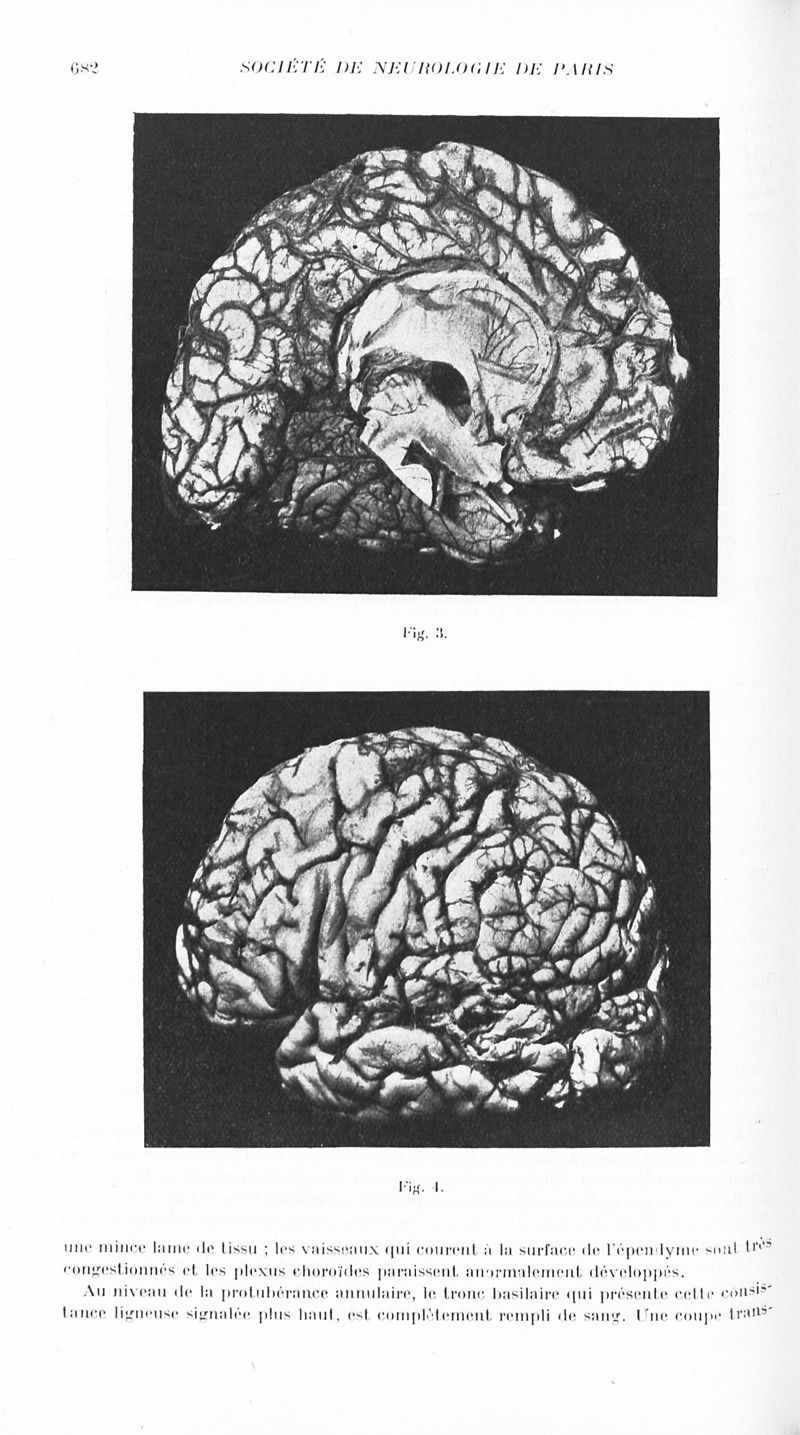

Revue neurologique

1935, vol 2. - Paris : Masson , 1935.